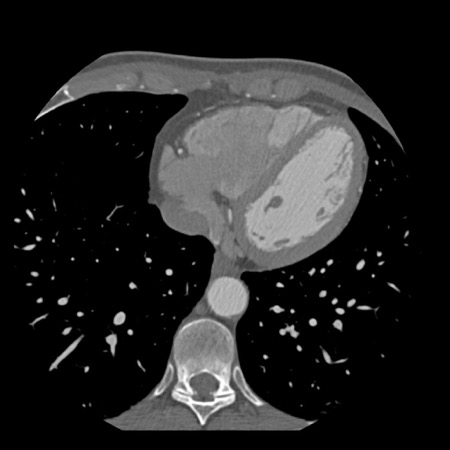

case 1 – CAD-RADS 2/P1

First, scroll through the scan.

Not all images are included. Some images without any abnormalities are skipped

from the series.

How would you describe the findings on the coronary CTA?

The findings are:

- Agatston score of

this patient was 14 (P1). Please, also note the calcification of the aortic valve. - Some partially

calcified and calcified plaques are present in the LAD with mild stenosis

(25-49%). - Calcified-plaque in

the LCX causing minimal stenosis (<25%). - Non-calcified

plaque in the distal RCA causing minimal stenosis (<25%). - This patient classifies

as CAD-RADS 2/P1, which means no further workup is needed.